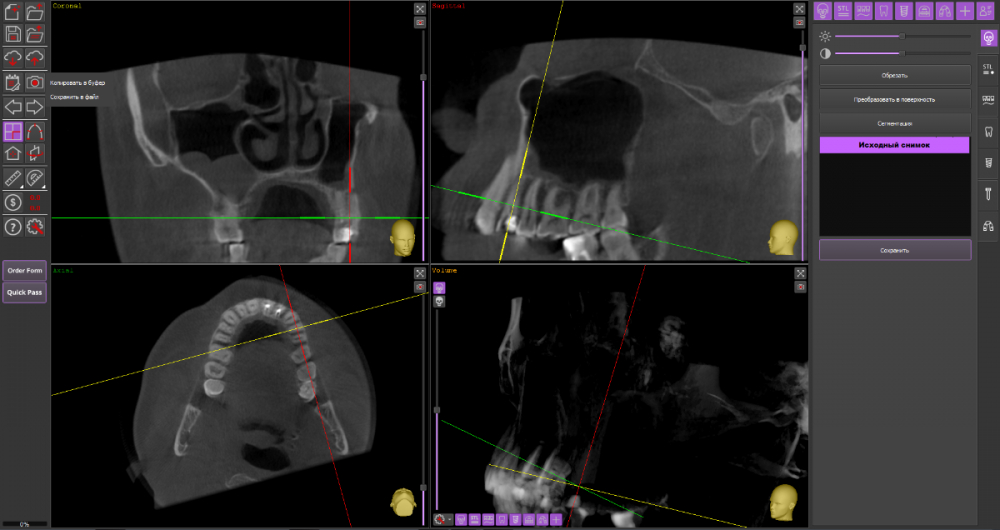

alexx123 Опубликовано 9 декабря, 2021 Поделиться Опубликовано 9 декабря, 2021 (изменено) Здравствуйте. 24-й зуб. Периодонтит осложненный периоститом. Посмотрите пожалуйста насколько реально сохранить зуб. Лечили в поликлинике глубокий кариес. Через несколько месяцев часть зуба откололась, появилось воспаление и позже на челюсти вылезла большая шишка. При этом боли не было. Зуб не шатался. Обратился в хорошую платную клинику. Абсцесс вскрыли, начали лечение эндо. Уже 4 раза чистили каналы. Положительная динамика вроде бы есть, но очень медленная. Есть ли смысл продолжать лечение или все же удалить? И еще вопрос, реально ли сделать резекцию верхушки корня? Хирург сказал, что скорее всего нет. КТ до начала лечения. https://cloud.mail.ru/public/Zfhf/NcjmRfbej Изменено 9 декабря, 2021 пользователем alexx123 Ссылка на комментарий